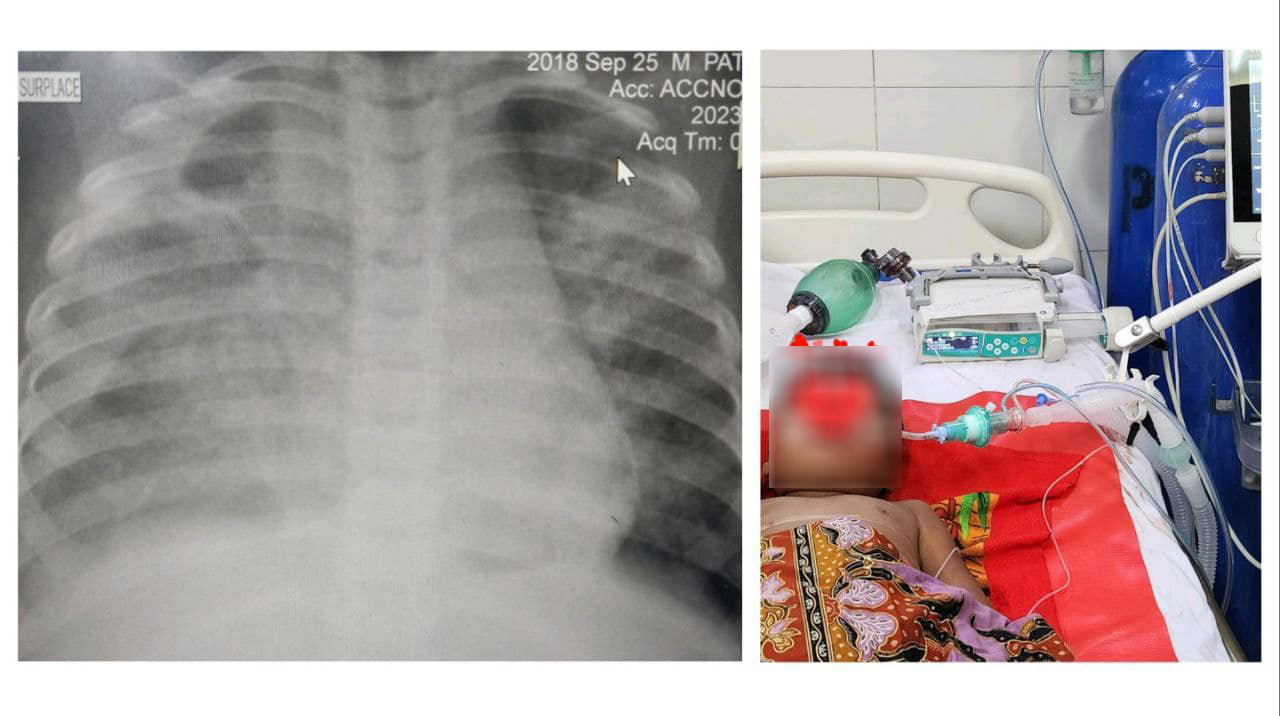

មន្ទីរពេទ្យគន្ធបុប្ជា បានបញ្ជាក់ឱ្យដឹងថា កុមារាតូចអាយុ៤ឆ្នាំ (EDS): អស់ជីពចរ សន្លប់ ហូរឈាម ខ្សោយដង្ហើម ខ្សោយថ្លើមនិងតម្រងនោម អស់ជីពចរ ៦ដង (6 times repeated cardiovascular collapses-shocks) ក្នុងរយៈពេល៤៨ម៉ោង នៅក្នុងបន្ទប់សង្គ្រោះបន្ទាន់នៃមន្ទីរពេទ្យគន្ធបុប្ផា ត្រូវបានសង្រ្គោះជីវិត ដោយប្រើឈាមនិងប្លាស្មាអស់ ៦ប្លោក និងបញ្ចូលប្លាកែតអស់៤ប្លោក ជាមួយការសង្រ្គោះដោយម៉ាស៊ីនសប់ដង្ហើម៣ថ្ងៃ។

ថ្ងៃនេះកូនតូច ត្រូវបានជួយសង្គ្រោះជីវិតនៅមន្ទីរពេទ្យគន្ធបុប្ផាភ្នំពេញ សូមអរគុណនិងកោតសរសើរដល់ក្រុមគ្រូពេទ្យឯកទេសសង្គ្រោះបន្ទាន់នៃមន្ទីរពេទ្យគន្ធបុប្ផាភ្នំពេញ ដែលបានសង្គ្រោះជីវិតមួយនេះ ពីករណីគ្រុនឈាមធ្ងន់ធ្ងរដ៏កម្ររមួយនេះ។